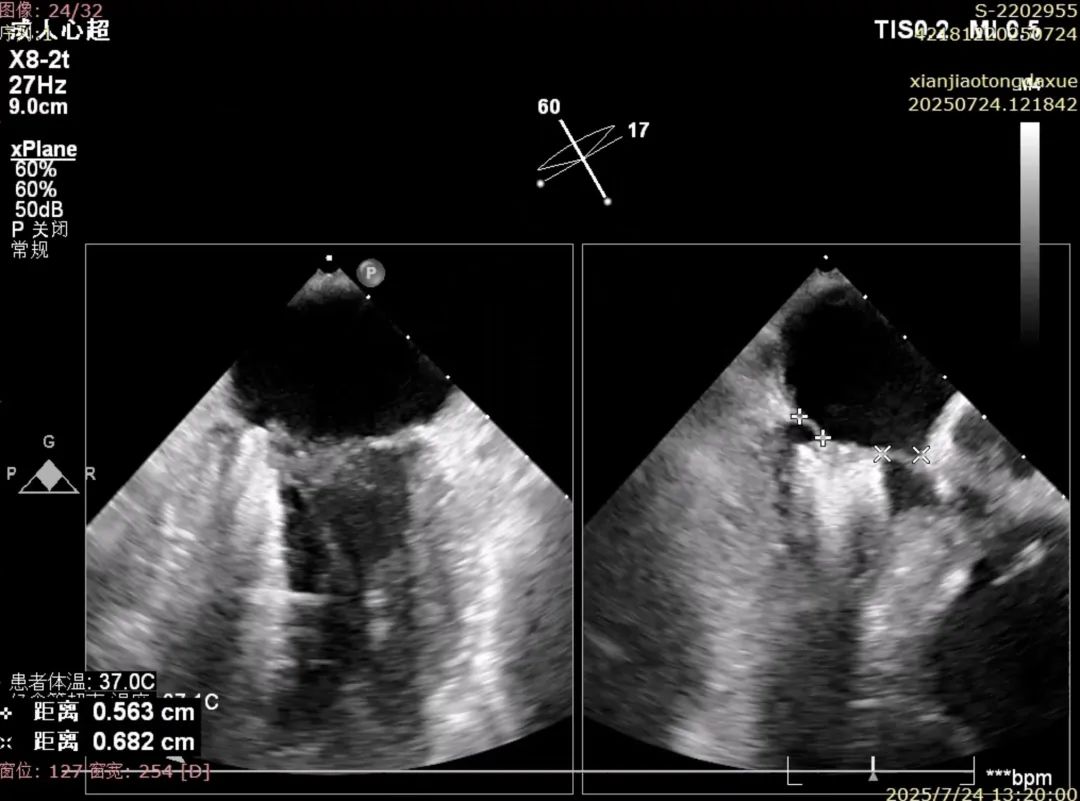

确认夹合位置及效果

术后夹合数据确认,达到预期效果